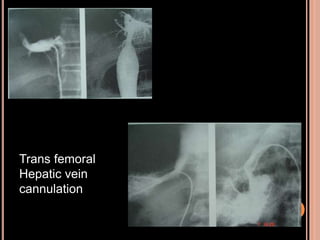

IDENTIFYING THE HEPATIC VEIN/S

Trans femoral

Hepatic vein

cannulation